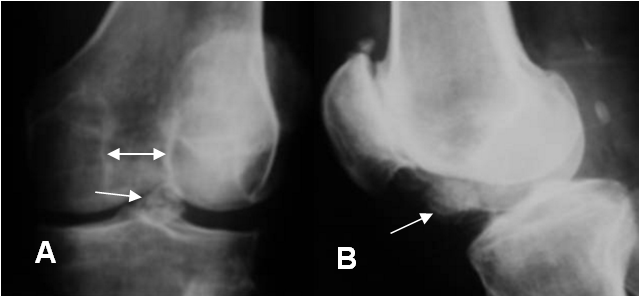

En la hemofilia se produce daño del cartílago, como reacción inflamatoria al sangrado repetido. Es frecuente en la rodilla, donde típicamente hay disminución simétrica del espacio articular y se ensanchamiento del espacio intercondileo. (3). (Fig 67, 68 A y B).

Fig 68 A. Artropatía por hemofilia.

A: Rx AP. Presencia de cuerpo libre calcificado (Flechas) y aumento del espacio intercondileo.

B: Rx lateral. Cambios degenerativos en la articulación femoropatelar.

Fig 68 B. Artropatía por hemofilia.

Rx de túnel. Osteopenia con aumento del espacio intercondileo y erosión de los cóndilos femorales y platillos tibiales.